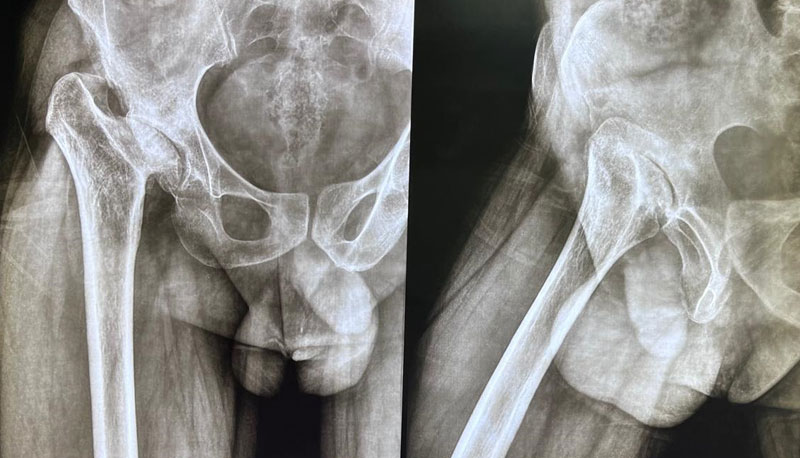

A 32-year-old male with a 7-year history of hip osteoarthritis underwent total hip replacement in 2018, with reconstruction of a false acetabulum using bone graft and screws. A recent X-ray shows a well-fixed implant in good alignment, and the patient reports pain-free walking with a good range of motion.